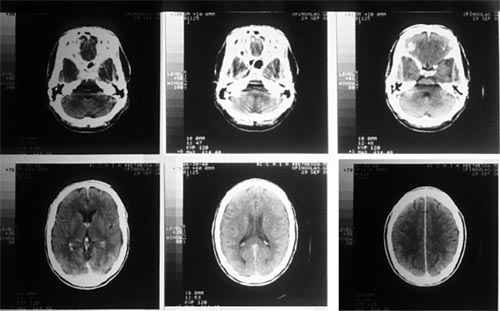

La tomografía computarizada vs la radiografía convencional

La radiografía convencional carece de la habilidad de dar información detallada acerca de las estructuras internas. Una gran limitación a los rayos x convencionales es que producen imágenes de dos dimensiones de estructuras de tres dimensiones. Adicionalmente, el cuerpo contiene varios tejidos que absorben a los rayos X de maneras y magnitudes similares; como resultado, la distinción entre estos tejidos en las las imágenes que se producen puede ser difícil. Para agregar, la radiografía con rayos X no es una ciencia exacta, pues muchos de los rayos X que se emiten se dispersan (rebotan y se alejan) del paciente, produciendo una imagen incompleta. La tomografía computarizada logra resolver este problema al generar imágenes en tres dimensiones de una estructura interna, y al detectar diferencias en la densidad estructural de los tejidos, y los rayos X pueden dirigirse a áreas específicas para obtener una imagen más clara.1

Imagen cortesía del NCI